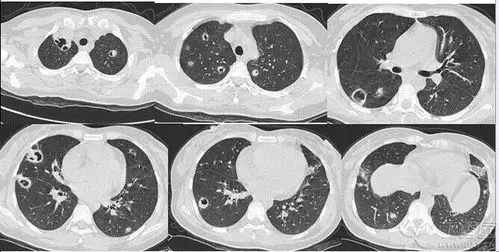

几组肺炎ct读片大畅带你来看图

新型冠状病毒肺炎ct片集锦早期和进展期有啥不一样